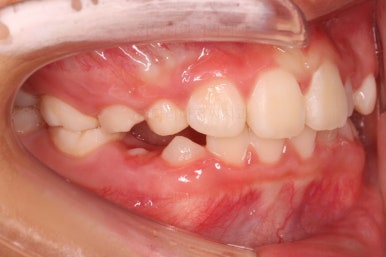

치료 시작 3개월째의 모습입니다.

윗니가 점점 앞으로 나오는게 보이실거에요. 사실은 치아가 나오는 것이 아니라 치아가 담겨있는 위턱뼈가 통째로 앞으로 나온 것입니다.

좀 더 하면 마무리를 할 수 있을 것 같네요.